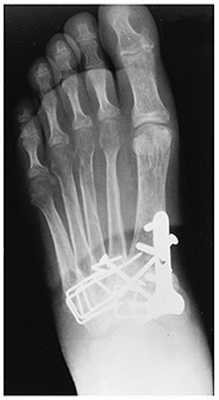

При смещении более 2 мм, нестабильности при функциональных тестах - рекомендовано открытое устранение вывиха с жёсткой фиксацией винтами или пластинами. Используются один или два продольных доступа в 1 и 2 межплюсневых промежутках. После обнажения первого предплюсне-плюсневого сустава первым этапом устраняется межклиновидная нестабильность, вторым этапом устраняется предплюсне-плюсневая нестабильность. В послеоперационном периоде сразу начинается разработка активного объёма движений. Нагрузку на стопу начинают постепенно, с тем чтобы полностью её восстановить к 6-8 неделе. Удаление спиц Киршнера производится через 6-8 недель, компрессирующих винтов через 3-6 месяцев. Возвращение к полной физической активности не ранее 9-12 месяцев после операции.

Открытое вправление вывиха, трансартикулярная фиксация 1-2-3 предплюсне-плюсневых суставов винтами.

После осмотра в отделении ортопедии №2 ГКБ №13 принято решение о проведении операции - открытому устранению вывиха, артродезе 1-2-3 плюсне-клиновидных суставов, 1 межклиновидного сустава при помощи винтов и пластины, трансартикулярной фиксации спицами 4-5 плюсне-клиновидных суставов.

Вершиной, ключом, блокирующим клином - в общем главной частью сустава Лисфранка является 2 плюсне-клиновидный сустав. По этой причине мы предпочитаем начинать фиксацию именно с него. Для артродеза используем винты с направленной в разные стороны резьбой FT Arthrex диаметром 4 мм. Они позволяют создать мощную межфрагментарную компрессию, а за счёт глубокой резьбы очень надёжно фиксируются в кости.

После восстановления 2 луча выполняем артродез межклиновидного сустава и 1 плюсне-клиновидного сустава. Учитывая что основная нагрузка ложится на 1 луч, дополнительно стабилизируем его при помощи пластины.